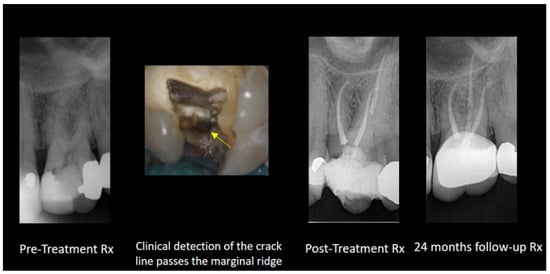

2.2. Cracked Tooth